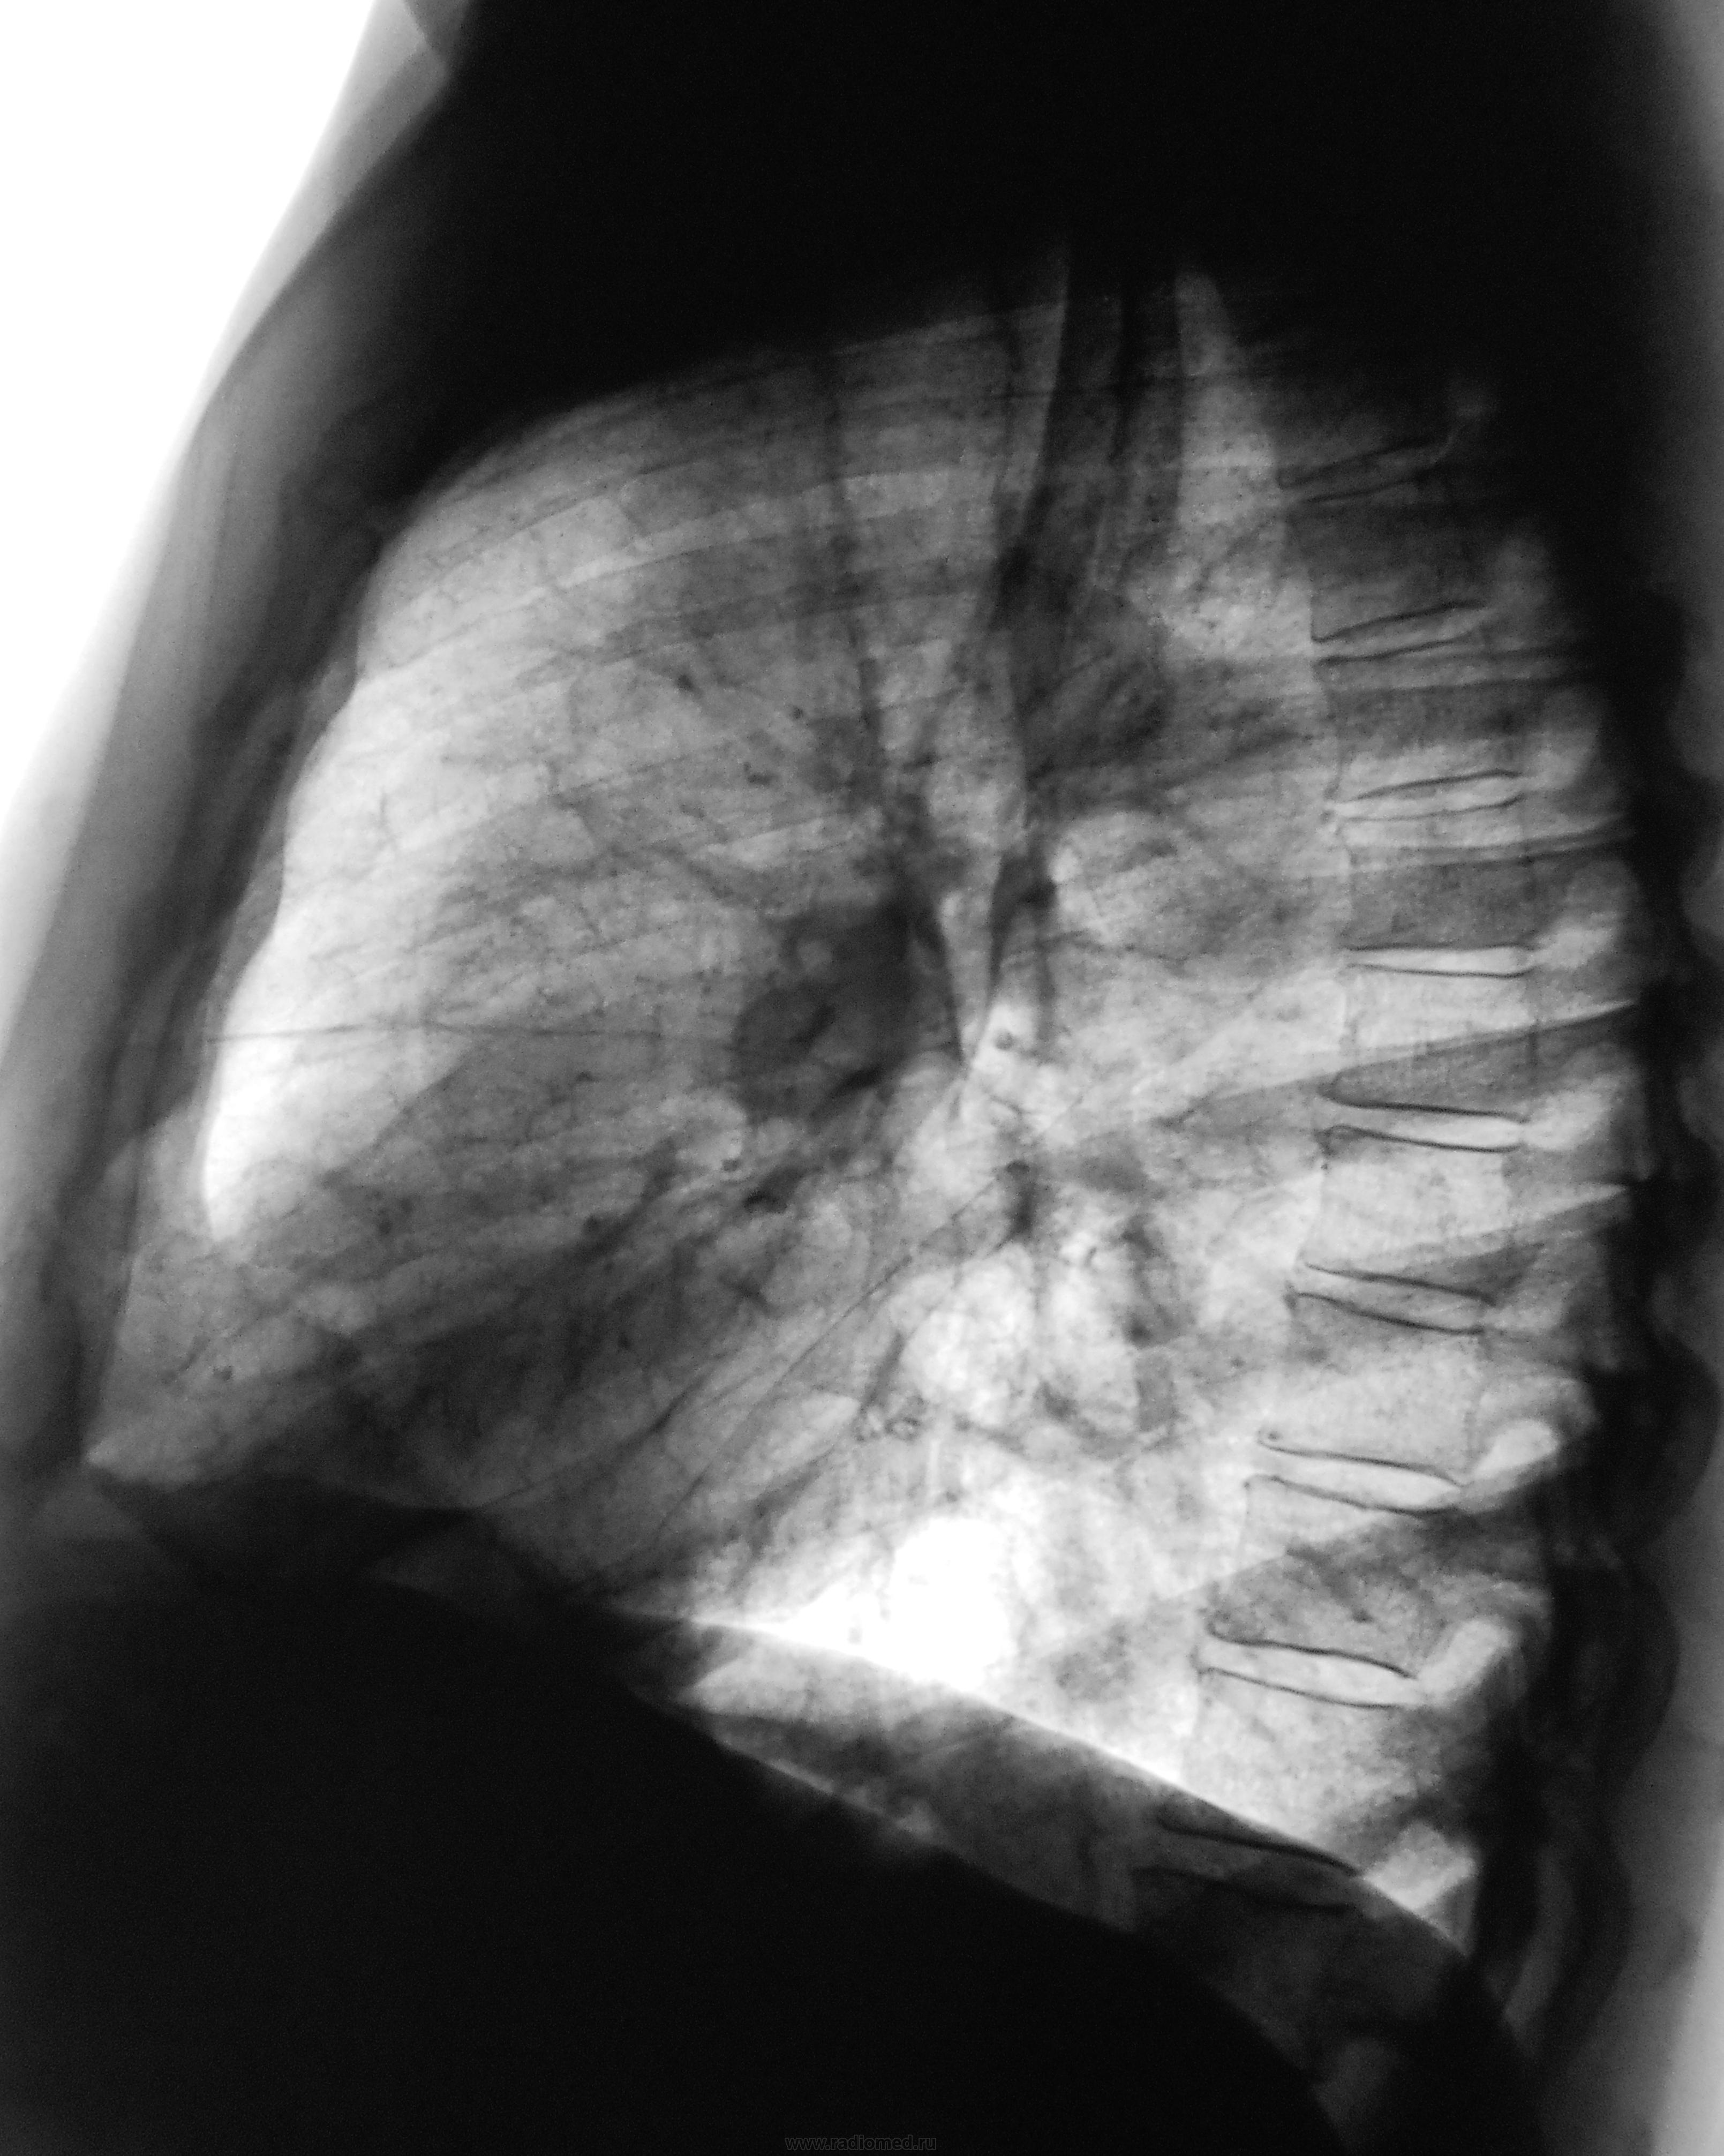

Пациент  из областной онкологической "конторы" направлен на рентгенографию ОГК (по месту жительства) с диагнозом "гамартома" - "шутка" № 1.

Меня сомнения обуяли по поводу гамартомы, и мы решили "порезать" линеечкой...

Однако пациент мне возразил и отказался от томографии, так как онкологи из областной "конторы" сказали ему, что томограммы ИМ не нужны, им хватит только снимков - прямой и боковой -

это "шутка" № 3 господ онкологов из "областной конторы"

"Гамартома" подозрительно быстро растет blush Как же это онкологи от варианта периферического рака так быстро отказались

По томограммам нет, а вот по снимкам даже вырезку Ринглера можно увидеть.

Это была "шутка" № 4. Онкологами "областной конторы" томограммы не рассматривались, диагноз "гамартомы" был выставлен только по рентгенограммам (пленочным), произведенным в их конторе.

Пациент был выявлен после флюшки в прошлом году, был дообследован рентгенографически и томографически, была рекомендована консультация специалистов "областной конторы", все цифровые изображения (снимки и томограммы) были записаны на "сидюшный диск", но специалисты "конторы" диск даже не смотрели, хотя он с протоколом исследования был у пациента наруках, и это была "шутка" № 5.